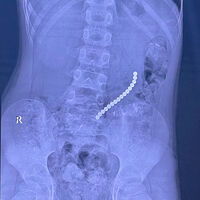

В Иркутске спасли восьмилетнего мальчика с 16 магнитами в желудке и кишечнике

Врачи Иркутской областной детской клинической больницы спасли восьмилетнего пациента, который проглотил магниты. Об этом сообщил главврач больницы, член-корреспондент РАН Юрий Козлов на своей странице во «ВКонтакте».

Медик отметил, что ребенок поступил в медучреждение с жалобами на «острый живот». На обследовании специалисты обнаружили 16 магнитов, которые соединились между собой в различных сегментах внутренних органов.

«Очень редкое сочетание: одни магниты находились в желудке, другие — в начальном отделе тонкой кишки. Это привело к образованию фистулы — сообщению между желудком и кишкой», — поделился Козлов.

С помощью технологий минимально-инвазивной хирургии врачи извлекли инородные предметы, разделили органы и восстановили их целостность.